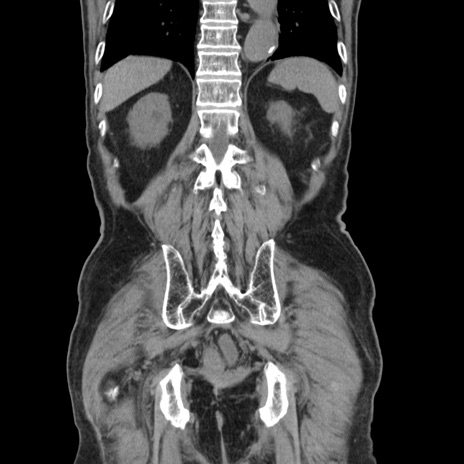

症例24(冠状断像)

【症例】80歳代男性

【主訴】左側腹部痛、嘔吐

【現病歴】本日早朝より左腹部に痛みあり。昼頃嘔吐認めたため、救急要請。

【既往歴】直腸癌(Mile手術)、胆摘

【身体所見】意識清明、BT 35.9℃、BP 221/93mmHg、SpO2 97%(RA) 、腹部:左ストーマ周囲に限局性の腹部膨隆あり。 膨隆部自発痛・圧痛あり・軟。

【データ】WBC 7700、CRP 0.09